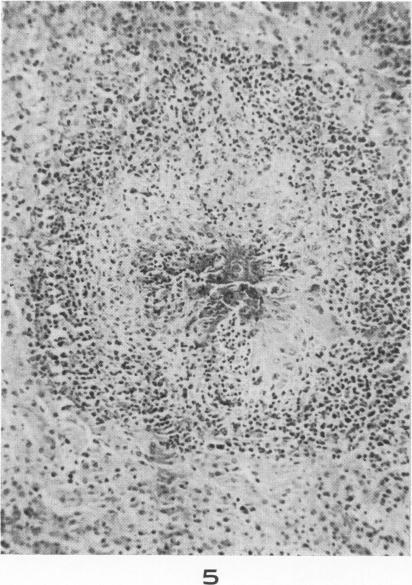

Visceral larva migrans; with a case report.

Am J Pathol. 1956 Jul-Aug;32(4):777-803.